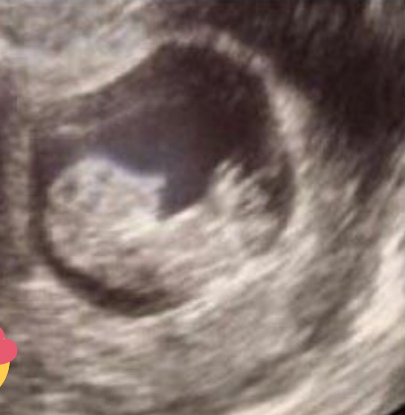

Además, la publicación divulgó que en el último ultrasonido que se realizó la primera dama de Chiapas el médico le dijo que era niño el bebé que está esperando, aunque no lo confirmó pues hay probabilidades de que no sea así. Todavía el pasado 23 de agosto de 2016 la ex integrante del grupo RBD, publicó una fotografía donde aparece con el abdomen marcado por el ejercicio que hace y la dieta que lleva, como tratando de despistar la exclusiva de su embarazo.